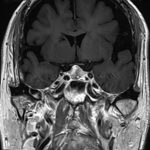

582

'24年10月

50代

頭蓋咽頭腫

頭蓋内腫瘍摘出術

No.’24_84 手術前1

No.’24_84 手術前2

No.’24_84 摘出 前

No.’24_84  摘出 中

No.’24_84 摘出 後